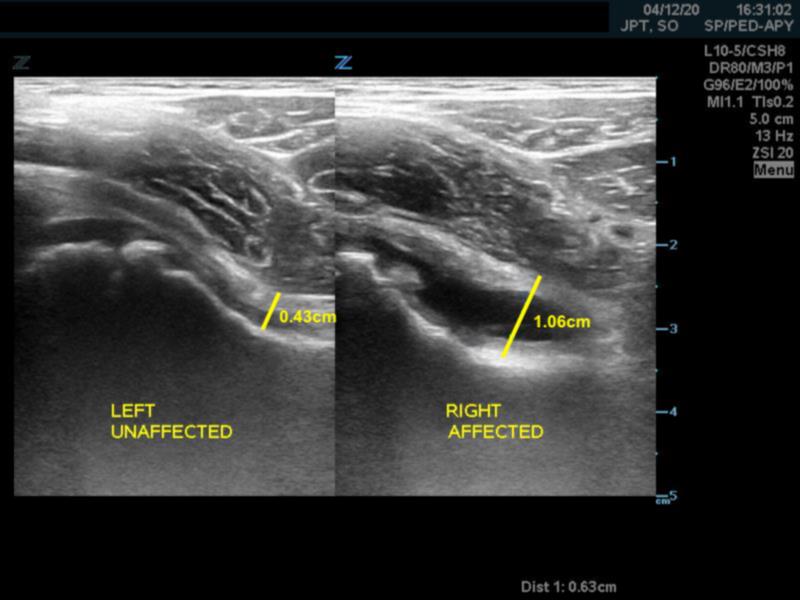

- A capsular-synovial thickness >5 mm, or >2 mm difference compared to the asymptomatic contralateral side indicates hip joint effusion in children

- Figure 4. Capsular-synovial thickness measurement >5mm in hip effusion (right)

- Joint capsule also appears convex instead of concave in case of effusion

- Figure 5. Hip without effusion (left) has a concave shaped joint capsule and hip with joint effusion (right) has a convex shaped joint capsule.